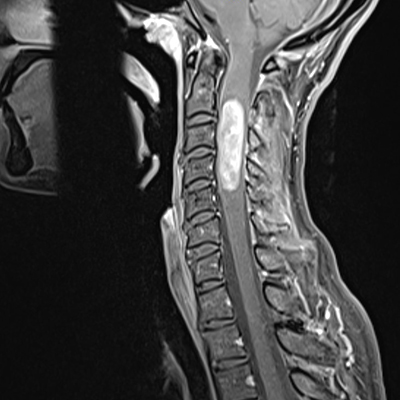

This MRI scan shows Devitt's tumor was in the upper region of her spinal cord, near the brain stem.

Doctors diagnosed Devitt with an intramedullary ependymoma, which is a cancerous tumor that grows within the spinal column, according to Moffitt Cancer Center neurosurgeon Dr. Andre Beer Furlan. It’s less common in adults than in pediatric cases, he said, and in Devitt’s case, it was high in her spinal cord.

“This was close to the brain stem so there were risks with surgery,” Beer Furlan said.

Those risks included partial- to full-paralysis or dangers to subconscious motor skills like breathing. The risks of not removing it were just as high because it was compressing the spinal column and nerves from within.